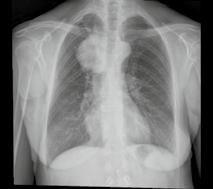

Longfoto en CT-scan van een 62-jarige patiënte die rookt en sinds enkele weken bloed ophoest. Ter hoogte van de bovenste kwab van de rechterlong is een massa te zien.

De PET-scan laat zien dat de massa verdacht is. Een biopsie bevestigt vervolgens het vermoeden van longkanker.